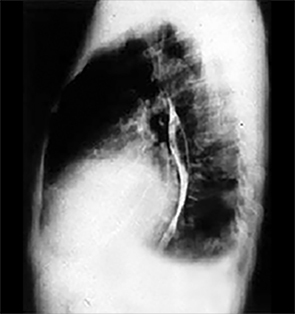

Our Patient's PA and Lateral

Click on the xrays to enlarge them.

Choose the best interpretation of the chest X rays:

Cardiomegaly, pulmonary venous congestion & pleural effusion